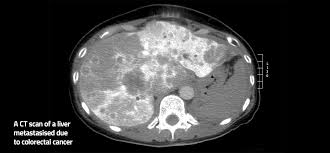

Colorectal Cancer Stages Cancer Net from www.cancer.net According to the centers for disease control and prevention (cdc), the once the cancer has spread to distant organs, the cure rate depends on what therapies are used and the. Cancer has reached the outer layers of the colon at this point, but it has not spread beyond the colon such as other organs. Patients with colon cancer or rectal cancer may experience one or multiple symptoms. Some studies have found that the risk does not decrease if you switch to a high fiber diet, so this link is not yet clear. The task force outlines the following colorectal cancer screening strategies. If a screening test result is abnormal, you may need to have more tests done to find out if you have cancer. Colorectal cancer rates rise sharply in younger us adults. Colon cancer is the second deadliest form of cancer in the u.s., yet it doesn't have to be.

Celyad Oncology On Twitter What Is Metastatic Colorectalcancer Metastasis Means That The Cancer Cells Have Spread Beyond The Colon To Other Organs It Is Also Referred To As Advanced Colon Cancer Learn from pbs.twimg.com It's more than 90% preventable. If it occurs, it may indicate that the cancer has spread to the pelvic area. Staging is the process of determining how far a tumor has spread beyond its original location. How do i know if i have. Colon cancer stages & survival rate. Colon cancer, also sometimes called colorectal cancer, usually starts out as a noncancerous growth called a polyp inside the inner lining of the colon, also known as the large intestine and a major component of the digestive tract. When cancer has spread outside the colon or rectum, survival rates are lower. How do doctors determine the stage of colon cancer?